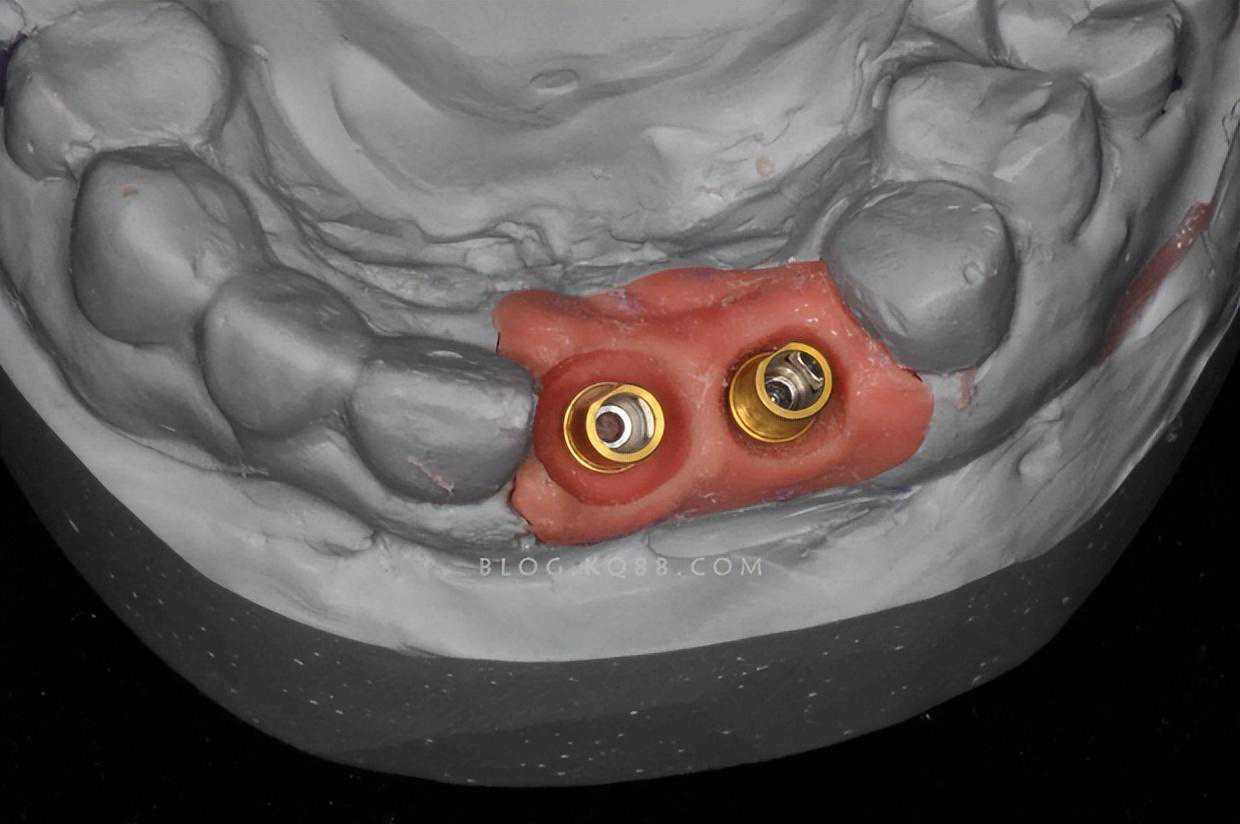

这一次,医生要做的就是塞块泥让你咬着,然后取出根据泥印做牙齿模型。做完模型,医院会把印模寄去工厂,由牙齿制作工厂根据印模做出适合你的牙冠。

取模

精准是指,传统手术在钻孔备洞时,大多凭借医生的个人经验,如果不是经验丰富的医生,可能会出现钻歪,深度不够,钻穿等问题。而数字化种植,会根据个人情况,通过数字化技术和3D打印技术定制种植导板辅助钻孔,保证钻孔的精确度和深度,一次成型。

数字化种植导板

安全是指,数字化种植导板的介入,保证备洞环节一次成型,将主观的人工操作变成客观引导,医生只需要通过种植导板下钻就行,不用担心钻偏、钻歪、钻穿等给患者造成伤害。